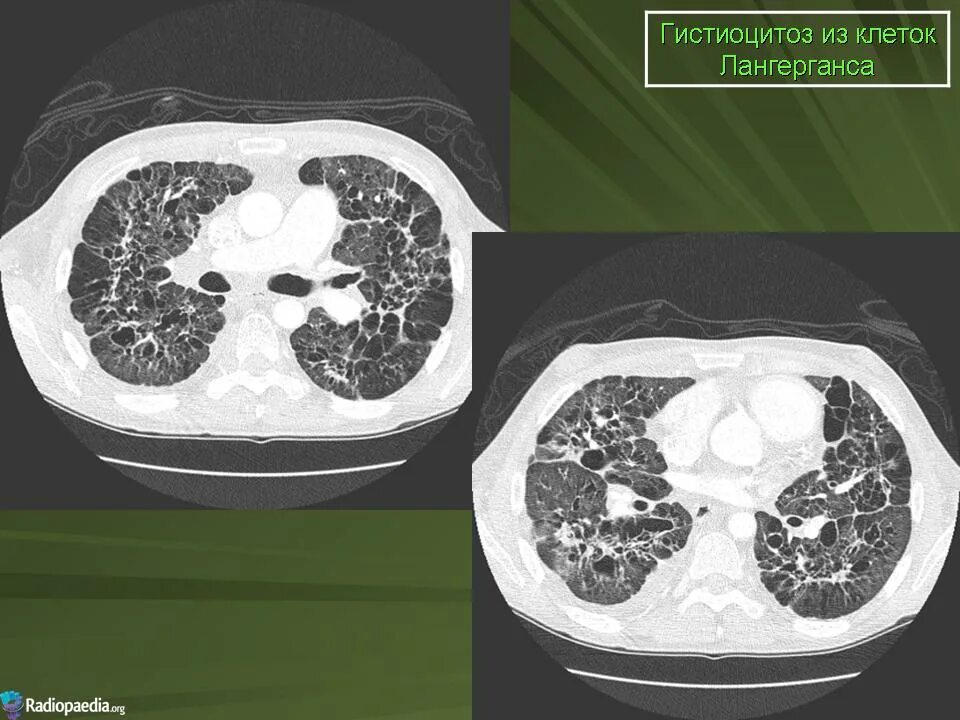

Кт х